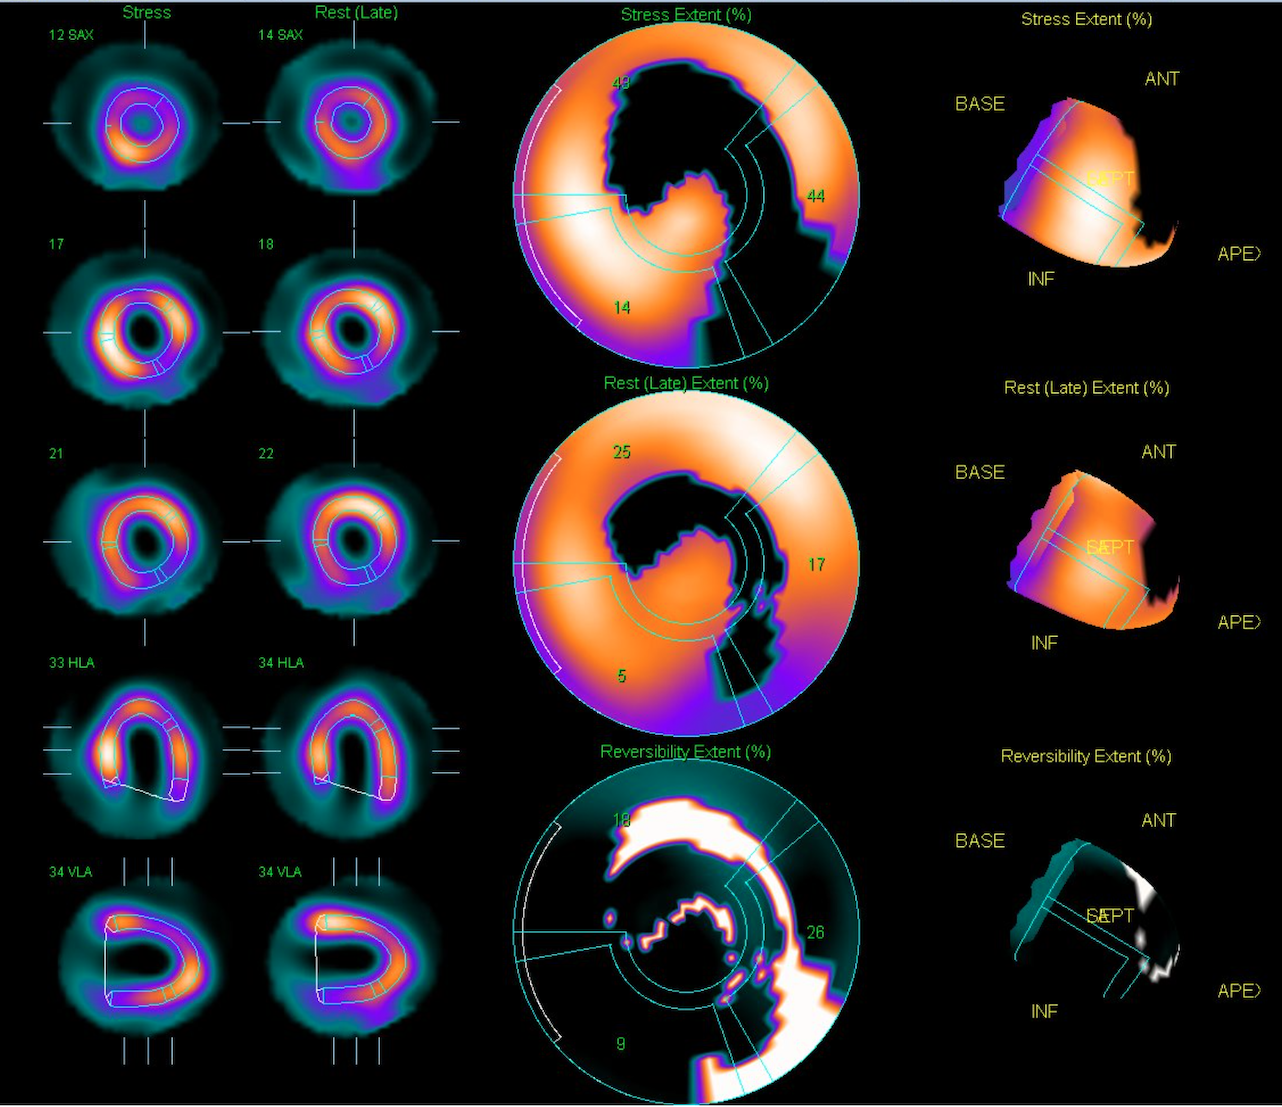

Echocardiography revealed inferior wall hypokinesis with a left ventricular ejection fraction of 47.1% by Simpson¡¯s method. Admission electrocardiogram showed normal sinus rhythm without significant ST-T changes. Thallium-201 myocardial perfusion scan demonstrated ischemia in the apical, inferior, anterior, apical/mid-lateral, apical-anteroseptal, and basal-inferolateral walls, with a total ischemic extent of 38%.